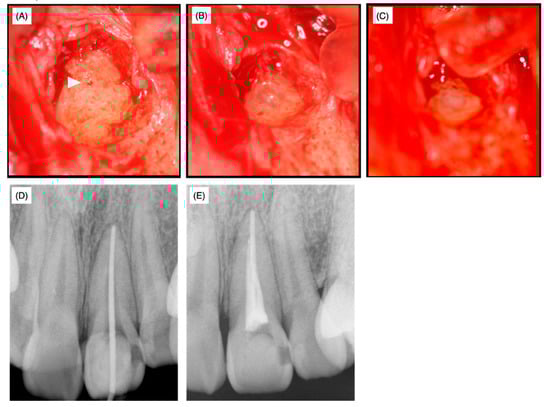

The medical histories of the patient and her family were non-contributory and no traumatic history of the frontal teeth was revealed by history-taking. At the time of the first examination at the university hospital, swelling was observed and the left maxillary incisor was discolored (Figure 2A).

At the time of the surgery, local anesthesia was administered, the target side was opened and granulation tissue was removed. The foramen of the accessory canal was identified by microscopy (Figure 4A, arrowhead) and the dentin tissue surrounding the foramen was drilled out using a diamond bur of 0.5 mm in diameter to remove potentially infected surrounding dentin (Figure 4B). After the cavity was disinfected with 10% sodium hypochlorite (NeoCleaner®, Neo Seiyaku, Nagoya, Japan) and washed with saline, a No. 25 K-file was inserted into the main canal in order to prevent resin material from leaking into the main canal, thereby preventing subsequent non-surgical endodontic treatment. Subsequently, the cavity was treated using a self-etching dentin-adhesive system (Clearfil MegaBond®, Kuraray Medical, Okayama, Japan) and filled with resin (Beautifil flow F02®, Shofu, Kyoto, Japan) (Figure 4C). Twelve days after the surgery, no swelling or clinical symptoms were observed, the sutures were removed and the affected area was irrigated with saline.

Over the next 40 days, supportive non-surgical endodontic treatment was conducted five times. At this stage, the root canal length was successfully measured and a working length of 25.0 mm from the top of the crown was set. The apex was enlarged until No. 55 with a K-file and the prepared root canal was irrigated with 3% EDTA solution (Smearclean®, Nippon Shika Yakuhin Co., Ltd., Yamaguchi, Japan). Calcipex II® was used as a drug for the root canal and glass polyalkenoate cement (Base Cement®, Shofu, Kyoto, Japan) was used as a temporary sealing. The fitness of the gutta-percha points (GC Dental Industrial Corp, Tokyo, Japan) in the apex region was examined (Figure 4D) and then the root was filled by the lateral condensation method using Grossman’s root canal sealer (Nishika Canal Sealer Eugenol Quick E-Q®, Nippon Shika Yakuhin Co., Ltd., Yamaguchi, Japan) (Figure 4E).

Figure 4. Operative photographs after granular tissue removal (A), after cavity preparation (B) and after sealing with composite resin (C). The arrowhead in (A) indicates the lateral foramen. X-ray films before (D) and after (E) root filling. The fitness of gutta-percha points in the apex was examined (D).